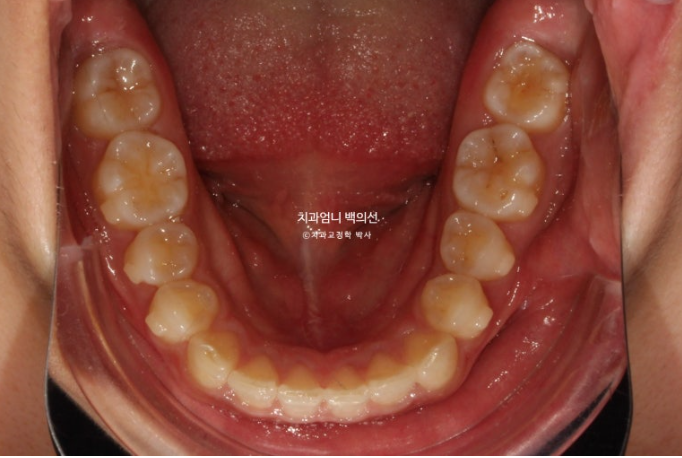

24년 7월까지, 첫 세트의 14개 장치를 모두 낀 후 모습입니다.

24.07

과개교합이 해소되며 아래앞니가 비로소 모습을 드러냅니다.

벌어진 틈을 깔끔하게 사라졌습니다.

삐뚤했던 앞니배열도 좋아졌습니다.

3.5개월의 변화라고 보기 힘들정도로 환자분은 열심히 껴주었고 치료계획도 완벽했습니다.